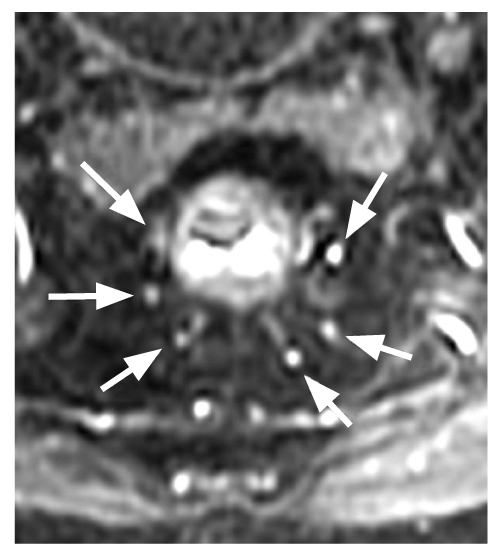

In all cases where interpretation was possible, six terminal branches of the superior rectal artery were identified, localized at 1, 3, 5, 7, 9, and 11 o’clock positions on the conventional dial (Fig. 2). Several anatomical variants of the upper rectal artery branching and its path to the rectal wall were revealed (Fig. 3 and Table 1). The superior rectal artery branches into three, with each branch subsequently splitting. This classical variant accounts for 54% of cases, as shown in Figure 3 (depicting the first, fifth, and sixth variants). Figures 4 and 5 are also included.

Fig. 2. Magnetic resonance tomography: 6 terminal branches of the superior rectal artery are visualized, located at 1, 3, 5, 7, 9 and 11 o`clock of the conventional dial.